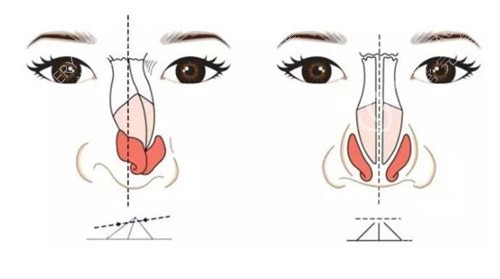

李海兵医生术后鼻型自然的秘诀在于他在意整体美学设计。

他不仅仅是单纯地修复鼻子,而是从面部整体协调性出发,根据患者的五官比例、面部轮廓等因素,设计出更适合患者的鼻型。

在手术过程中,他采用精细的操作手法,尽量减少对鼻部组织的损伤,确保术后修复快,并且能够呈现出自然逼真的结果。